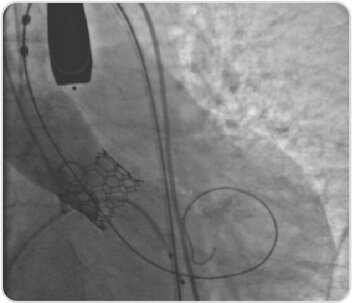

80 years old lady presented with effort intolerance of 6 months duration. Evaluated and found to have severe calcific aortic stenosis and normal coronaries. TAVI done successfully with 21.5 mm balloon expandable Myval (Meril, India).